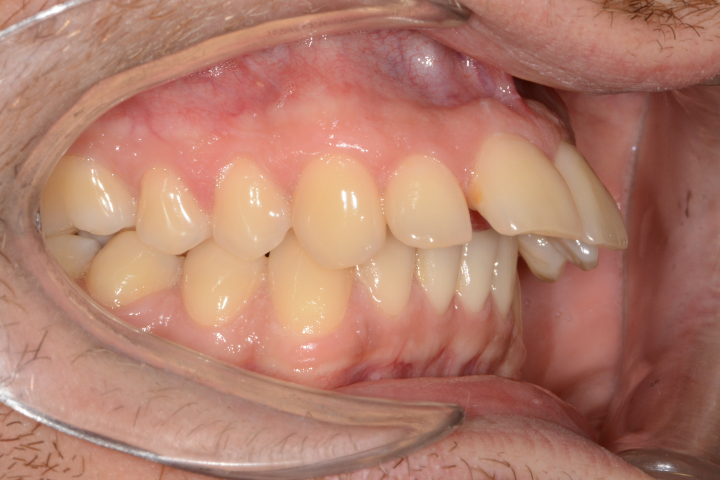

Az elmúlt évekből rengeteg szakmai referenciát tudnánk bemutatni, amelyek különböző fogszabályozási problémákat oldottak meg. Válogatva a több száz esetből, ezen az oldalon olyan képeket, információkat igyekeztünk bemutatni, amelyeknek a segítségével a jövőbeni pácienseinknek azt tudjuk üzenni: A Te fogsorod is lehet gyönyörű!

(Képeket a Pácienseink külön írásos beleegyezésével mutatjuk be!)